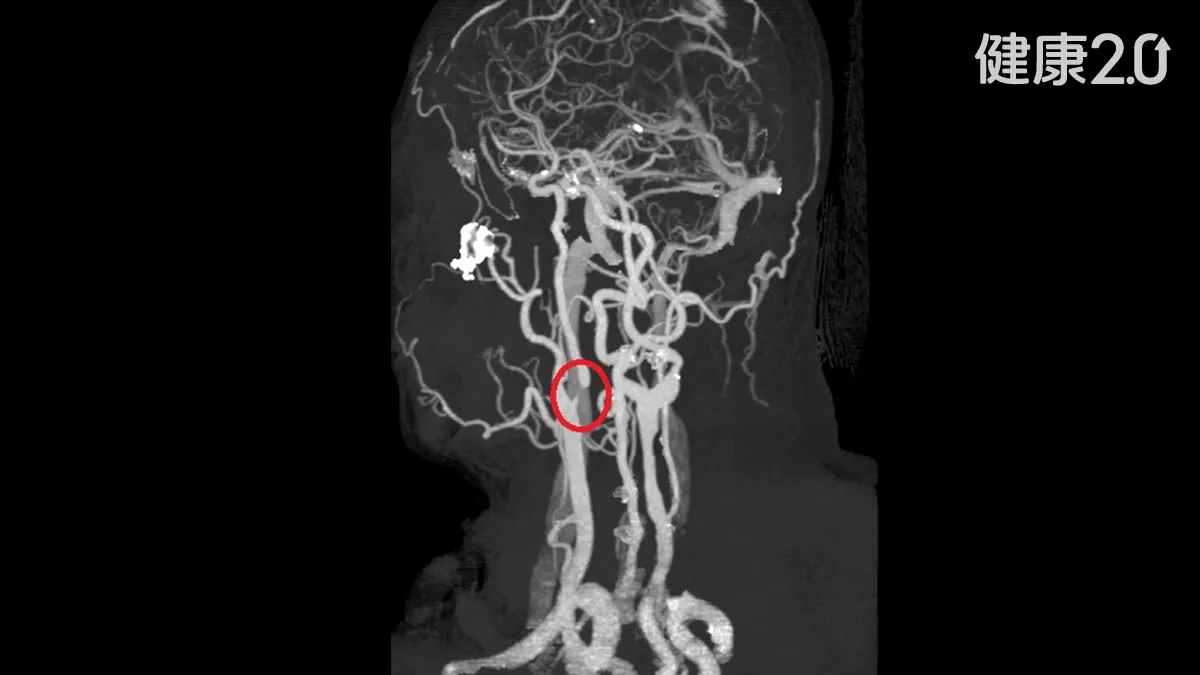

②冠心病

男女的冠心病很不相同,謝安民解釋,主要可能受到男性荷爾蒙和女性荷爾蒙影響;後者被認為對心血管有保護作用,前者反之。另外,女性心肌梗塞的人比男性少,尤其是停經以前,女性第一次發生心肌梗塞的年齡要比男性慢上9年左右,而停經以後的女人,冠心病罹患機率也迎頭追趕。他補充,若女性罹患糖尿病,保護傘幾乎不存在。